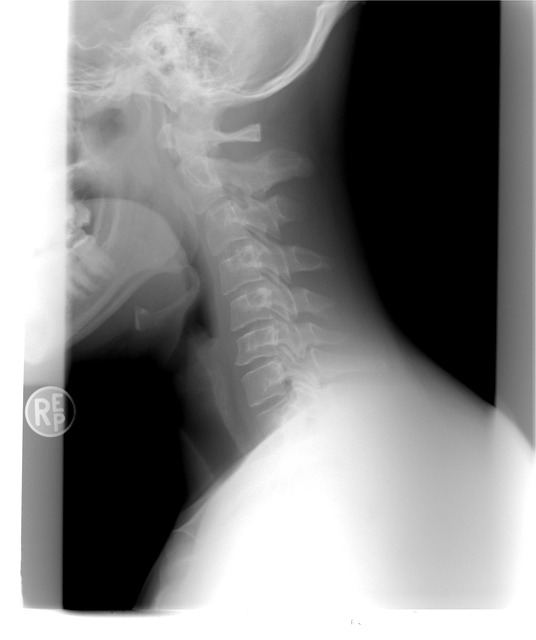

주변을 보면 갑상선 관련 질환 이야기를 흔히 들을 수 있어요. 갑상선은 목 앞부분에 위치한 기관으로, 신진대사에 필요한 여러 호르몬을 분비하는 매우 중요한 내분비선입니다. 특히 '목 부 음' 증상을 경험하는 분들도 있는데, 이는 갑상선에 이상이 생겼을 때 나타나는 대표적인 증상 중 하나입니다.

목 부 음 증상은 흔히 “갑상선종(甲狀腺腫)”이라 불리는 상태에서 나타날 수 있습니다. 갑상선이 비정상적으로 커지거나 혹이 생기면 목이 부풀어 보이거나 이물감이 느껴지고, 심한 경우 음식 삼키기나 호흡에 불편함을 겪기도 합니다.

목 부 음 증상이 있으면 병원에서 혈액검사를 통해 TSH, T3, T4 등 갑상선 호르몬 수치를 확인합니다.